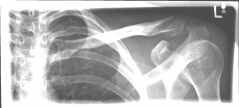

Acromioclavicular (lateral clavicular fracture), should be treated surgically, as a conservative therapy often leads to the formation of a so-called pseudarthrosis. Various implants are available, such as the hook plate and an anatomically preformed angular stable lateral clavicle plate.

Pictures: Here, an angle-stable plate was used to supply the clavicle fracture near the shoulder joint. This plate makes it possible to anchor many screws in the fragment and thus obtain a good stabilization.